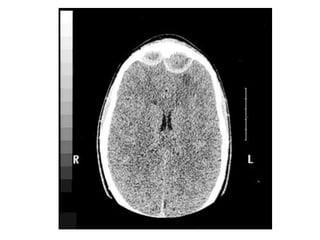

This document discusses sinus imaging using CT scans. It first describes the different sinus cavities in the anatomy: frontal, maxillary, nasal, ethmoid and sphenoid. Second, it lists common sinus pathologies seen on CT such as sinusitis, fungal sinusitis, deviated septum, sinus polyps, mucoceles, concha bullosa and sinus cancer. Finally, it presents two case studies and asks questions to test understanding of sinus conditions and anatomy.